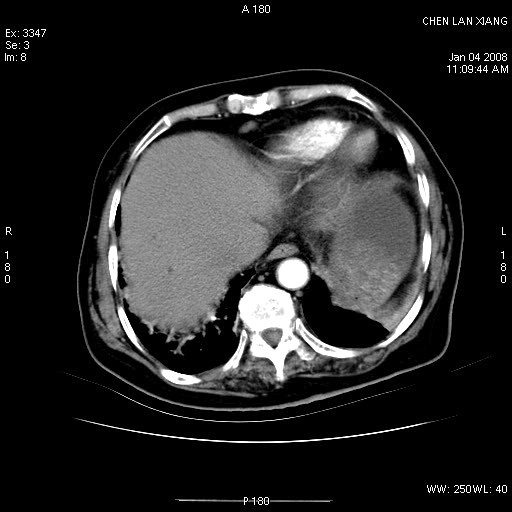

女,76岁,腹痛3-4天,b超示:肝内实性肿物,胆囊强回声,胆总管扩张.

1 胆总管末端结石伴肝内胆管结石,肝内外胆管扩张。2 胆囊扩大,胆囊壁不规则增厚,内见软组织密度影。考虑:慢性胆囊炎,不除外胆囊癌!

胆总管及肝内胆管多发性结石并扩张。

ct所见:1、 肝内胆管结石,肝内外胆管扩张。低位胆道梗阻,胆总管下端结石;2 胆囊扩大,胆囊壁不规则增厚

考虑:胆总管下端结石并肝内外胆管扩张,肝内胆管结石;

慢性胆囊炎

1)胆囊癌伴肝脏转移。2)胆总管下端结石、肝内胆管结石伴肝内外胆管扩张。